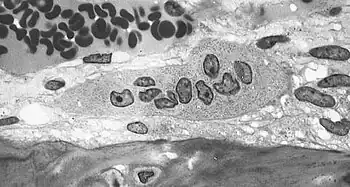

-

Light micrograph of an osteoclast displaying typical distinguishing characteristics: a large cell with multiple nuclei and a "foamy" cytosol. -